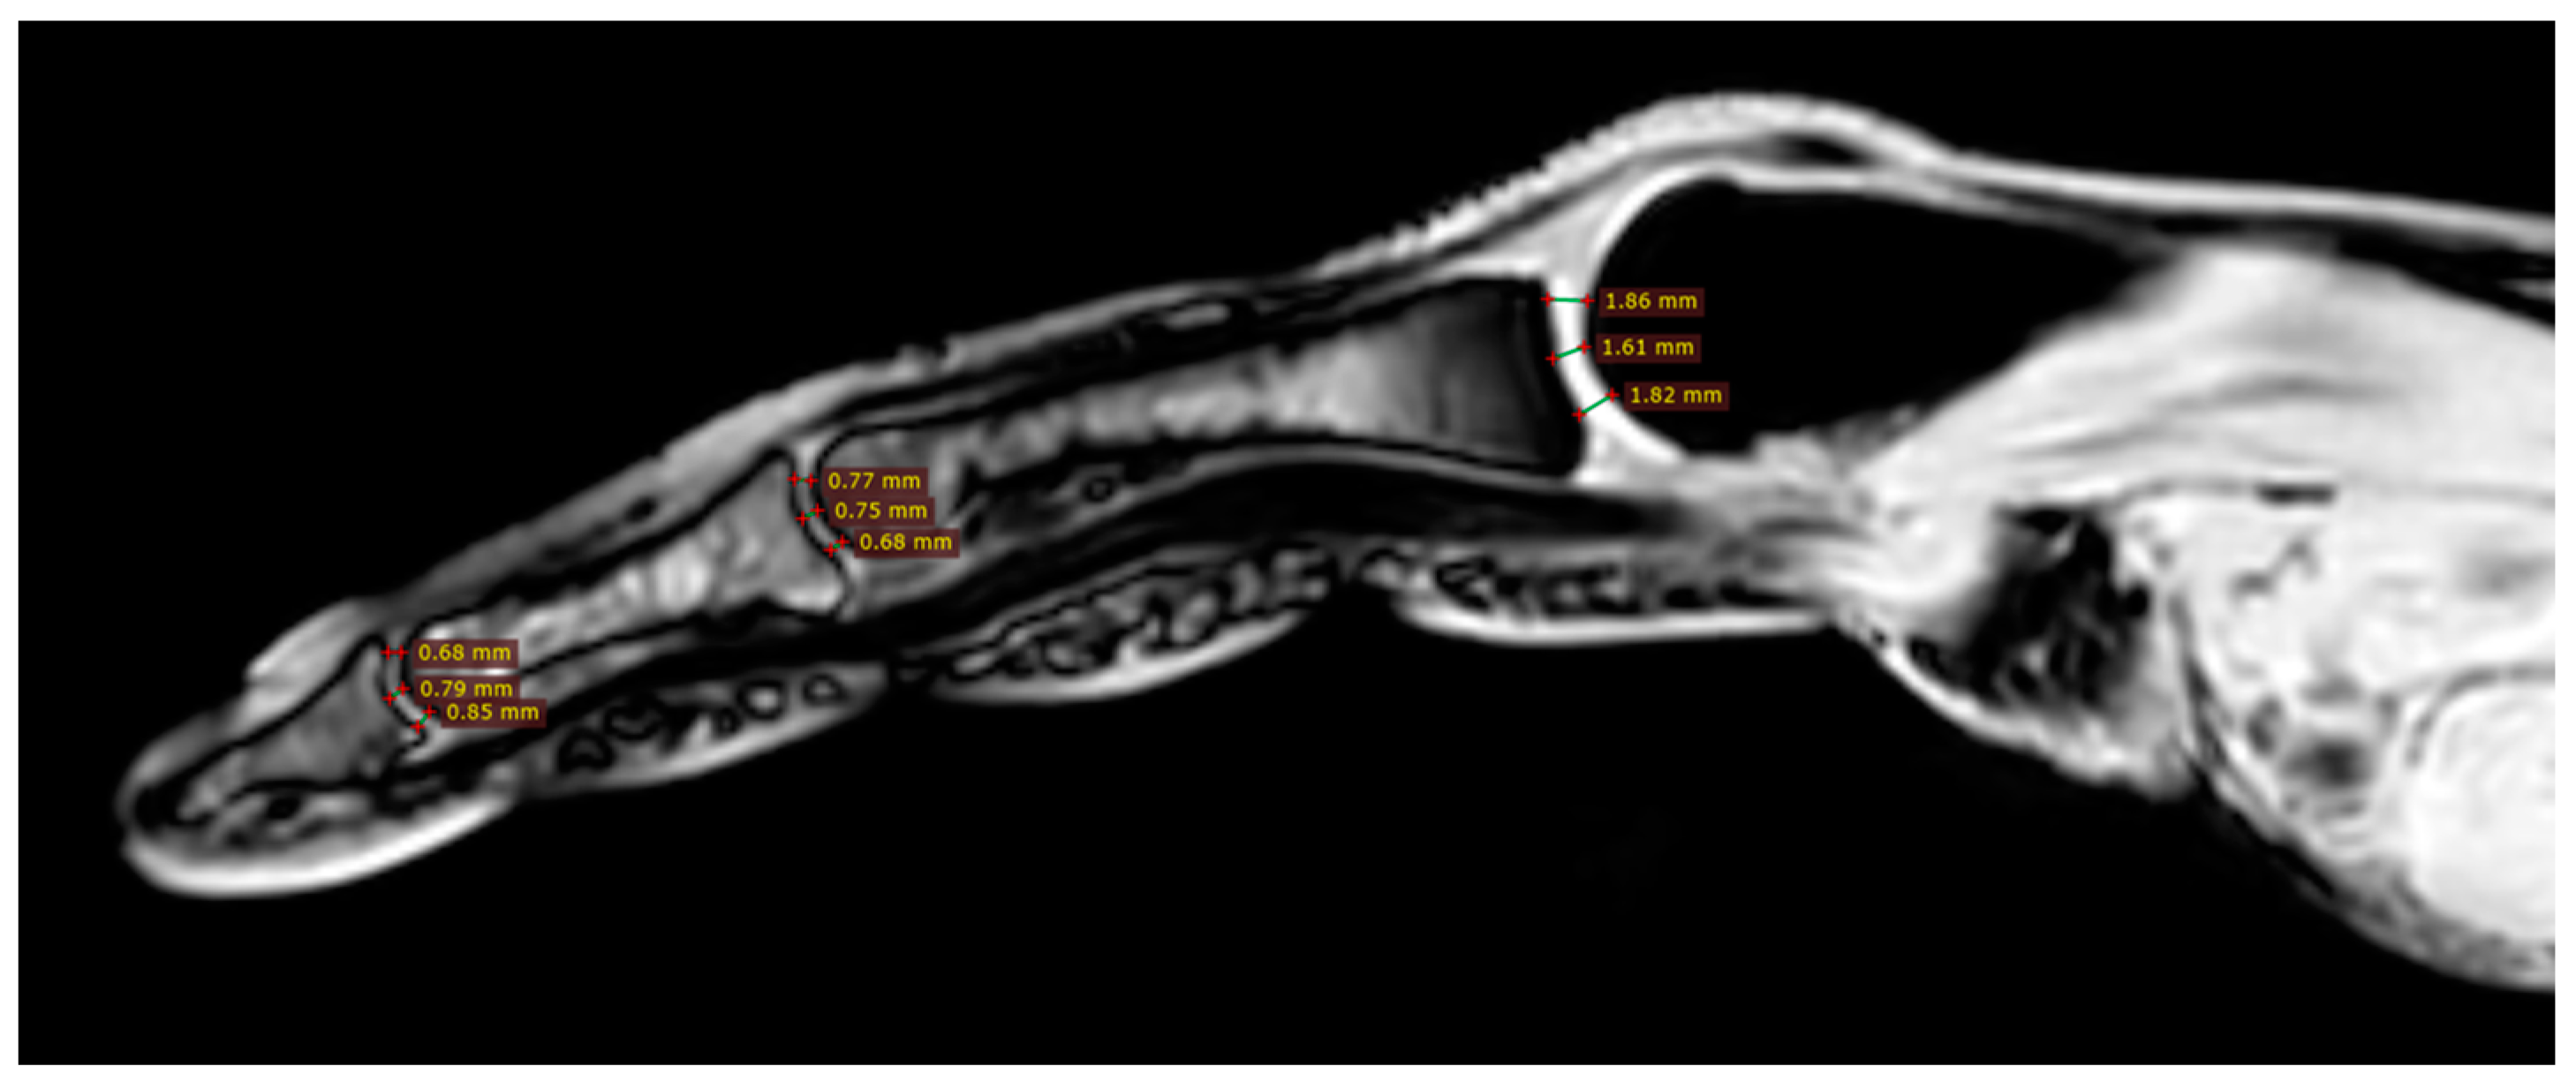

Cartilage Thickness and Distal Phalanx Length in MRI

| Finger | Parameter | Scleroderma | Control | p-Value |

|---|---|---|---|---|

| 1 | DPL | 16.9 (5.5) | 19.0 (1.2) | 0.4309 |

| IPJct | 0.8 (0.2) | 0.8 (0.1) | 0.7929 | |

| MCPJct | 1.1 (0.1) | 1.1 (0.1) | 0.6365 | |

| 2 | DPL | 12.7 (5.2) | 15.8 (1.4) | 0.4008 |

| DIPJct | 0.7 (0.3) | 0.8 (0.1) | 0.4948 | |

| PIPJct | 0.9 (0.5) | 0.9 (0.2) | 0.3720 | |

| MCPJct | 1.4 (0.3) | 1.5 (0.3) | 0.5635 | |

| 3 | DPL | 14.0 (4.6) | 15.1 (1.0) | 0.8748 |

| DIPJct | 0.7 (0.3) | 0.7 (0.2) | 0.7132 | |

| PIPJct | 0.8 (0.2) | 0.8 (0.1) | 0.7132 | |

| MCPJct | 1.2 (0.2) | 1.1 (0.1) | 0.9581 | |

| 4 | DPL | 16.4 (1.5) | 15.3 (0.9) | 0.3720 |

| DIPJct | 0.9 (0.2) | 0.9 (0.1) | 0.9581 | |

| PIPJct | 0.9 (0.2) | 0.8 (0.4) | 1.0000 | |

| MCPJct | 1.1 (0.3) | 1.1 (0.2) | 0.9581 | |

| 5 | DPL | 15.1 (1.5) | 15.0 (0.8) | 0.7527 |

| DIPJct | 0.8 (0.2) | 0.8 (0.2) | 0.9164 | |

| PIPJct | 0.9 (0.2) | 0.8 (0.1) | 0.4309 | |

| MCPJct | 1.2 (0.2) | 1.0 (0.2) | 0.0929 |